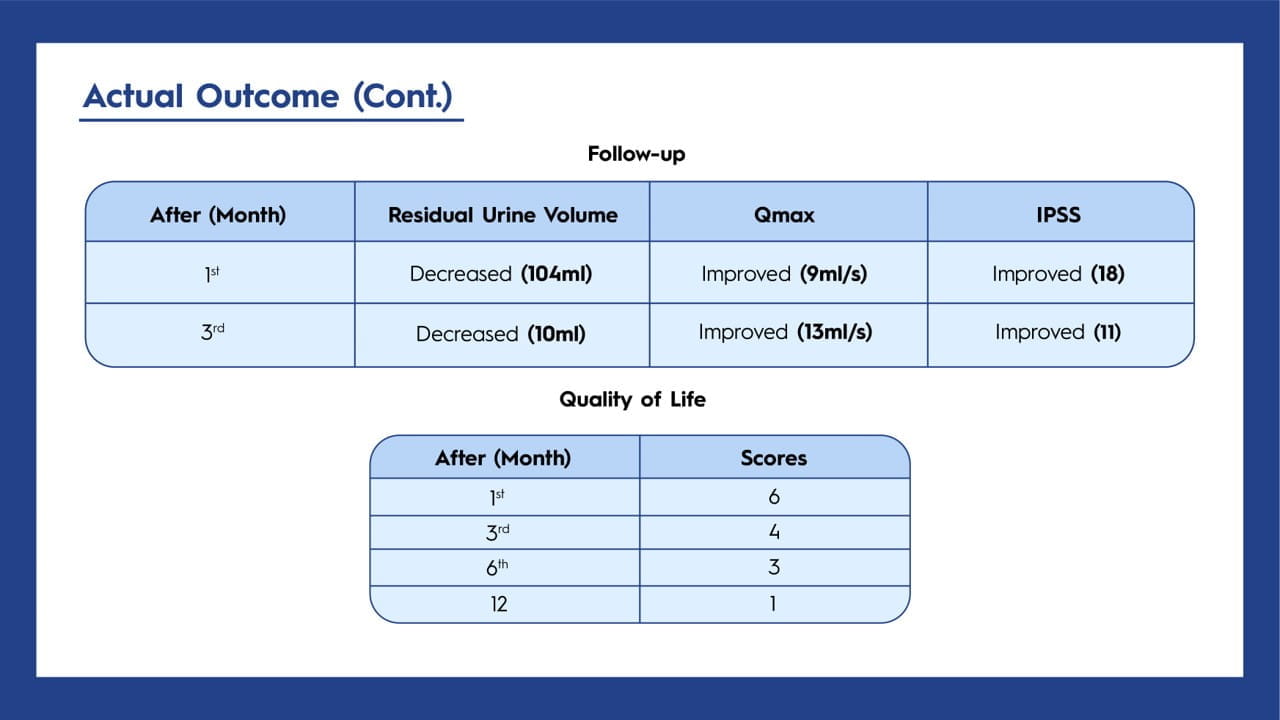

BPH, a common condition in older men, can occasionally progress to giant prostatic hyperplasia, where the prostate gland exceeds 500 g. Surgical options may be considered for complications that are challenging to manage with medication. In this case study, the patient successfully underwent a transvesical prostatectomy to treat a significantly enlarged prostate weighing 600 g.